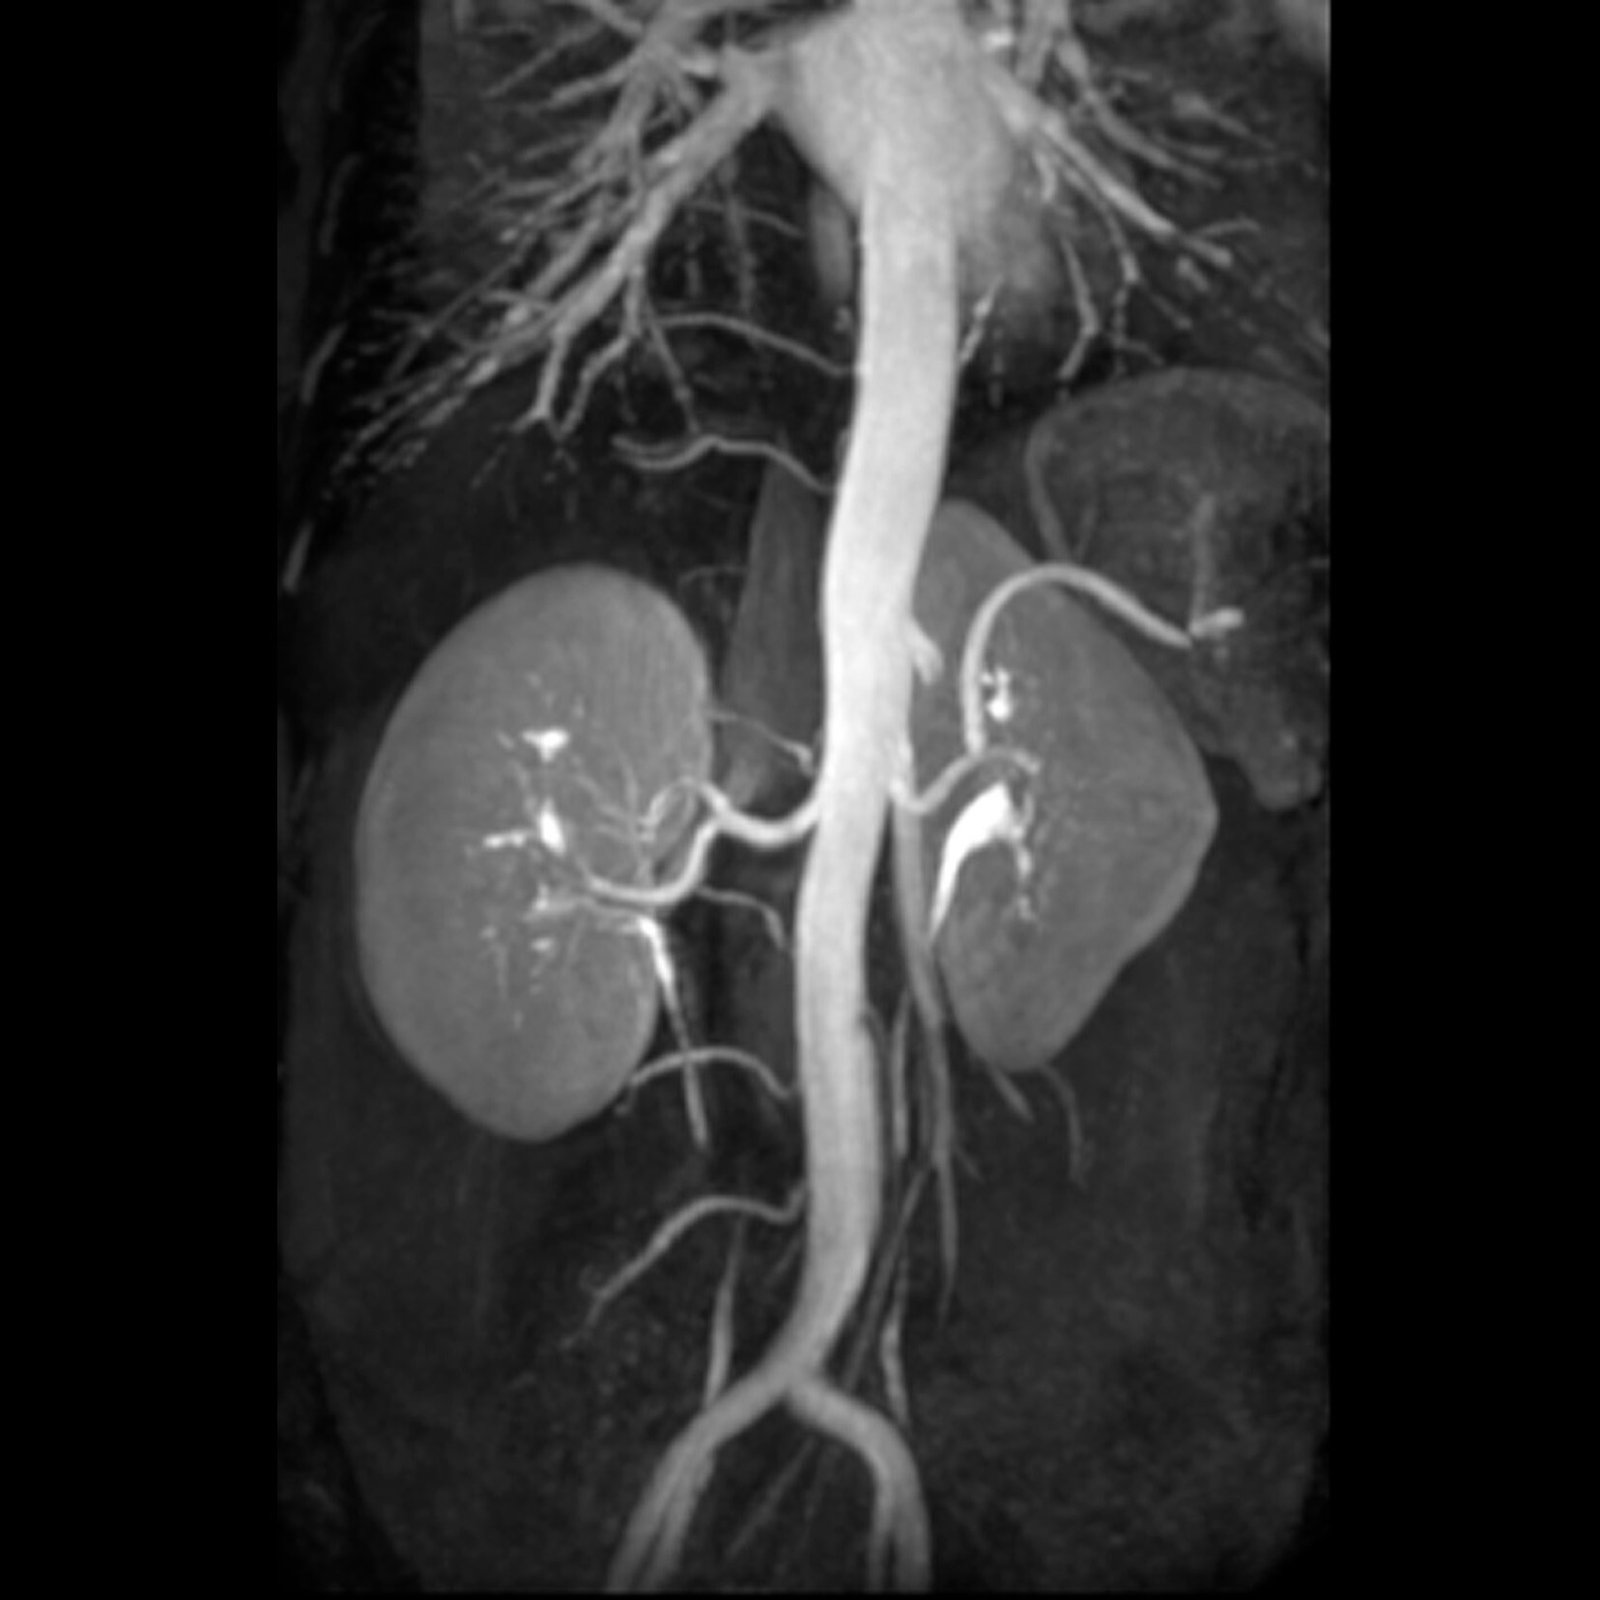

Vascular